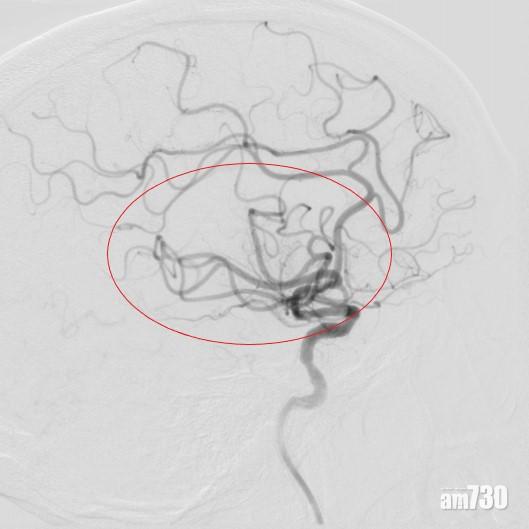

病人接受磁力共振或電腦掃描灌注造影(包括腦部及腦血管掃描),以確定血管阻塞位置。